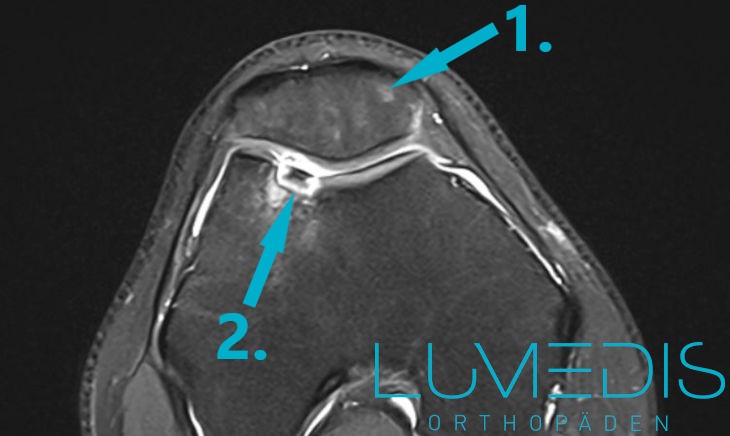

MRT: Osteochondrosis dissecans der Trochlea

Das MRT dient vor allem zur Diagnostik von freien Gelenkkörpern, die nicht röntgendicht sind.

Um eine erhöhte Aussagekraft zu erreichen, sollte ein 3 Tesla Hochfeld-MRT der neuesten Generation verwendet werden.

Trotzdem kann es manchmal schwierig sein einen freien Gelenkkörper durch das MRT zu sehen.